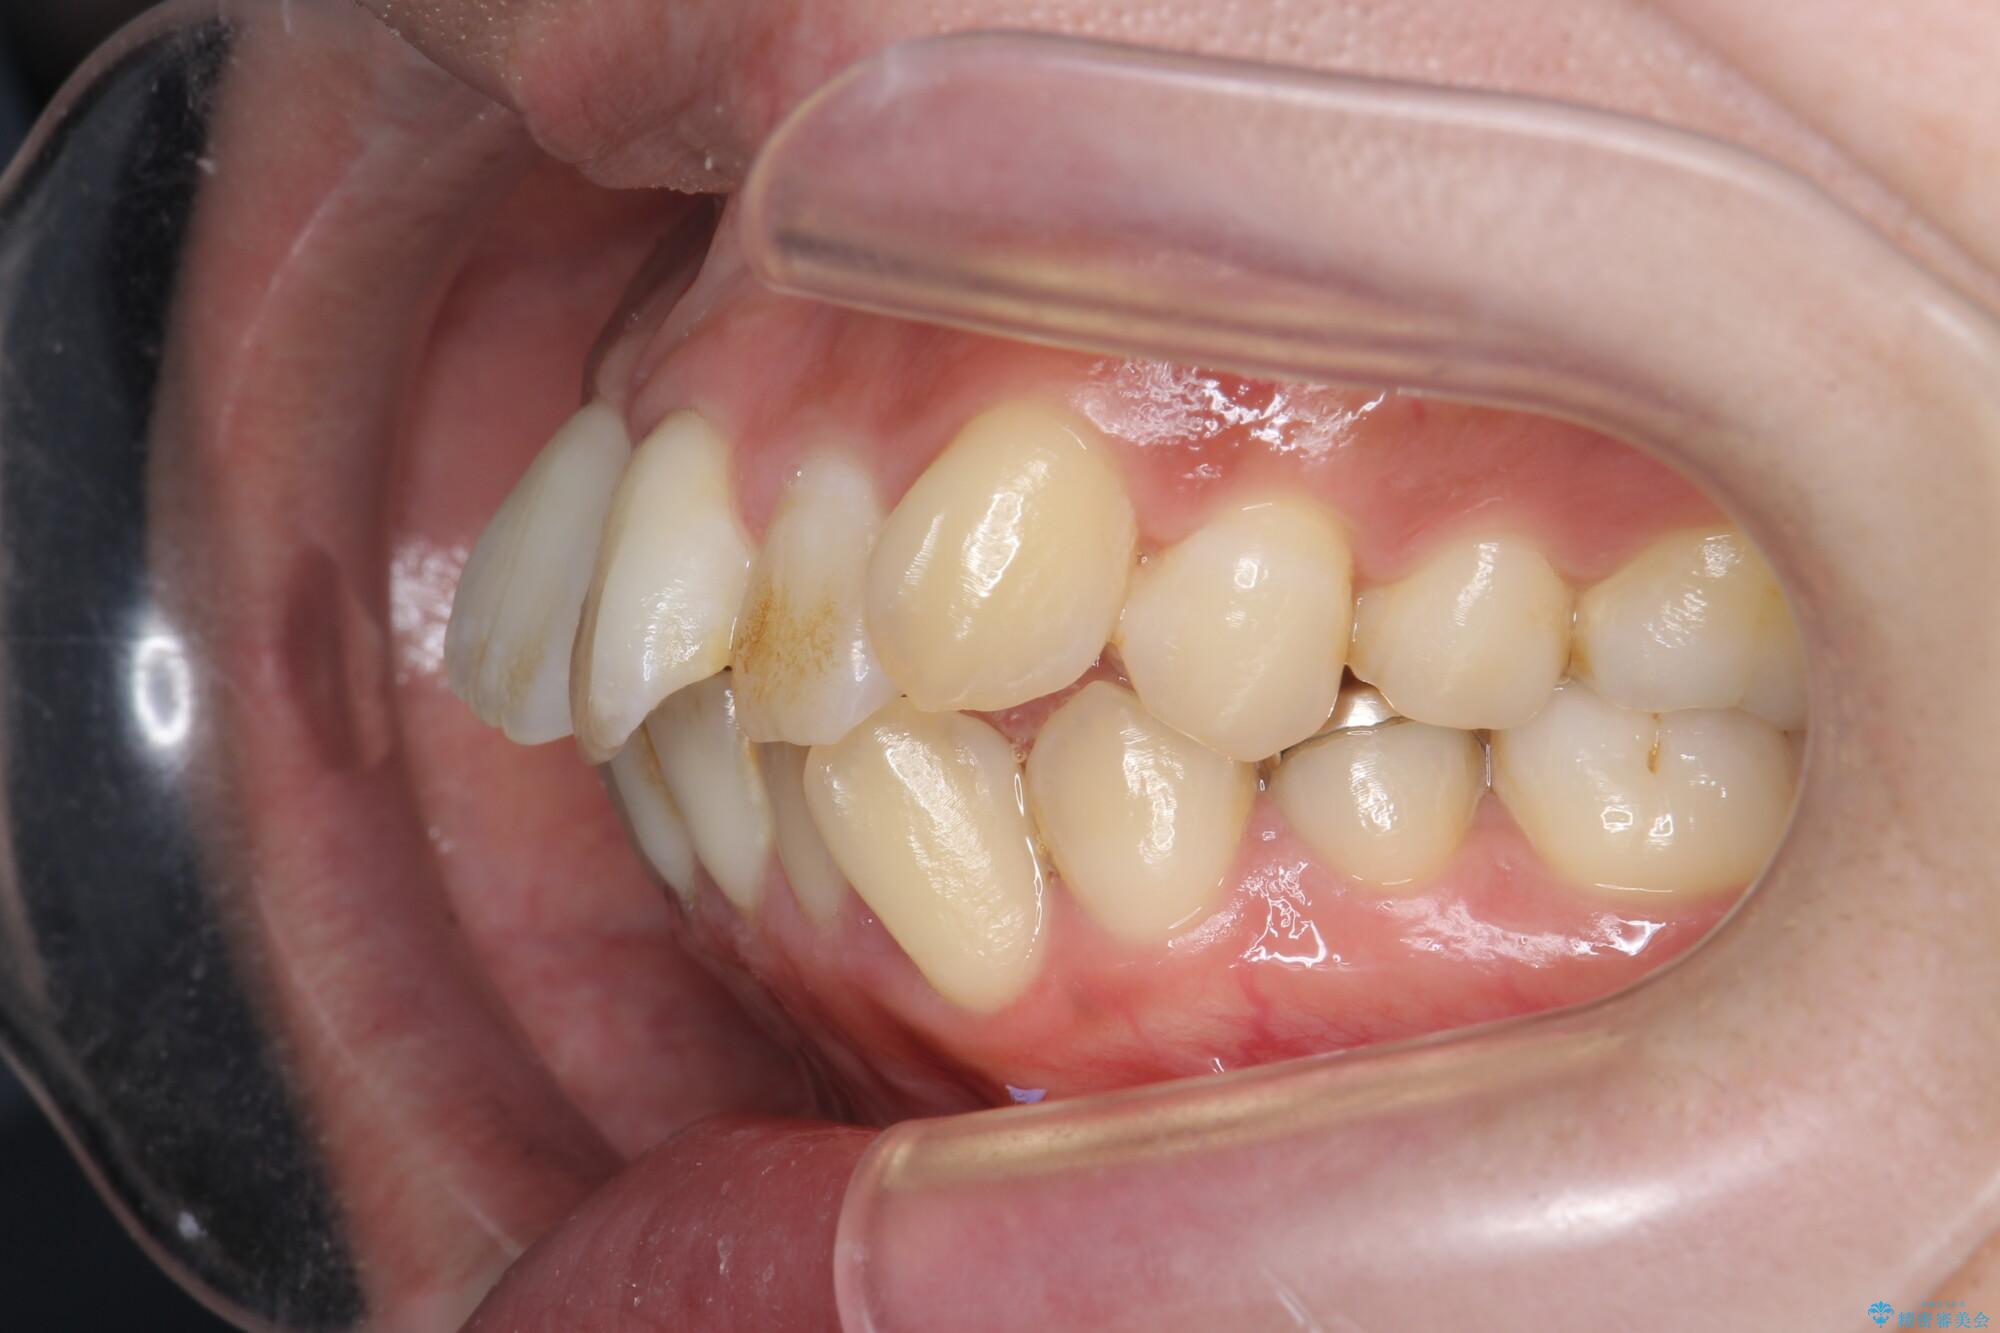

前歯のガタつきの改善を主訴にご来院されました。 特に犬歯の傾きが気になるとのことでした。

犬歯がかなり手前に傾いていましたが、ガタつきはそれほど強くないため非抜歯でマウスピース矯正が可能と判断しました。

治療前

気になる犬歯のガタつきをマウスピース矯正で改善 治療前画像 気になる犬歯のガタつきをマウスピース矯正で改善 治療前画像 気になる犬歯のガタつきをマウスピース矯正で改善 治療前画像 気になる犬歯のガタつきをマウスピース矯正で改善 治療前画像